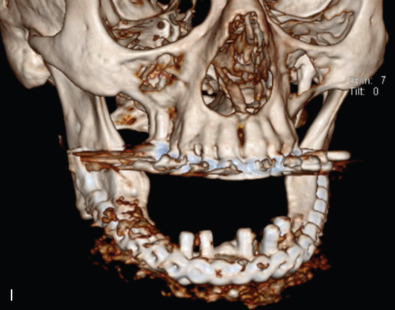

All of these systems allowed for convalescent function – life without MMF. RIF had the potential of dramatically shortening the course of treatment. However, its use was highly technique-sensitive with a steep learning curve. Thus, the incidence of complications increased dramatically due to operator error. Complications related to inadequate reduction – “the OIF” (open internal fixation … without the reduction) ( Figs. 1.16.1–1.16.3 ), inadequate fixation ( Figs. 1.16.4–1.16.7 ) and surgical misadventure ( Fig. 1.16.8 ) began to appear. Indeed, by the early 1990s operator error was the number one cause of mandibular fracture complications. Quite obviously, RIF is very unforgiving. When done poorly, one has a rigidly fixed mistake. The latest series of misadventures are related to the use of IMF screws. Bone-anchored arch bars will most likely be next. Not all believe that RIF and convalescent function is cost-effective with respect to the increased cost, potential for complications, and patient acceptance.

As has been noted, this largely depends on what one considers a complication. Some feel that minor complications – loss of teeth, exposure of hardware, exfoliation of bone and modest delay to union – do not count, so long as union and some semblance of functional occlusion is achieved. Others consider complications to include anything that delays union or results in a suboptimal result. For example, transoral miniplate fixation of angle fractures has a 22% minor complication rate – exposure of hardware, loose screws, wound dehiscence – which can be simply managed in an office setting and do not affect the final outcome. The same treatment has a low (2%) major complication rate requiring return to the OR and major surgery in the form of application of additional RIF and/or bone graft.